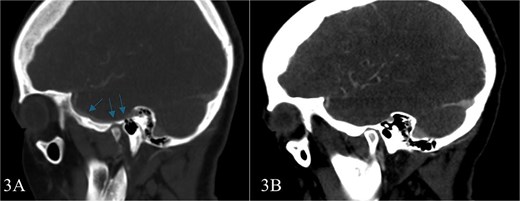

Subsequent MRI showed no evidence of meningocele or cephalocele, confirming an unremarkable intracranial evaluation (Fig. 2).To further evaluate potential vascular anomalies, a diagnosis of possible vascular compression over the ossicles was considered. Consecutive images from late arterial phase CT scan revealed the vascular nature of observation which drain into dural venous sinus (Fig. 3). A 3D cerebral angiogram was performed and confirmed the presence of a venous protrusion in the middle ear; however, the venous protrusion was not accessible for endovascular ligation due to its anatomical location and limited accessibility, making the risk of failed intervention high. Multidisciplinary discussions were held to consider management options, including middle ear exploration with attempted dissection of the venous anomaly from the ossicles. An alternative approach discussed was attic bypass via incus dislocation followed by ossiculoplasty. Given the patient’s stable condition and minimal impact on quality of life the patient preferred to pursue conservative management with hearing amplification and was scheduled for ongoing follow-up.

Consecutive images from late arterial phase CT scan reveals; the vascular nature of aforementioned observation which drain into dural venous sinus.